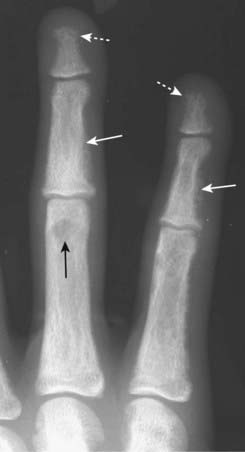

imageSome of the findings of hyperparathyroidism on conventional radiographs:

image Overall decrease in bony density

image Subperiosteal bone resorption, especially on the radial side of the middle phalanges of the index and middle fingers (Fig. 21-14)

image Erosion of the distal clavicles (Fig. 21-15)

image Well-circumscribed lytic lesions in the long bones called brown tumors and a salt-and-pepper appearance of the skull (Fig. 21-16)

image

Figure 21-14 Subperiosteal resorption in hyperparathyroidism.

The radiologic hallmark of hyperparathyroidism is subperiosteal bone resorption, seen especially well on the radial aspect of the middle phalanges of the index and middle fingers (solid white arrows). Here the cortex appears shaggy and irregular, compared to the cortex on the opposite side of the same bone which is well defined. This patient also displays two other findings of hyperparathyroidism: a small brown tumor (solid black arrow) and resorption of the terminal phalanges (acroosteolysis) (dotted white arrows).